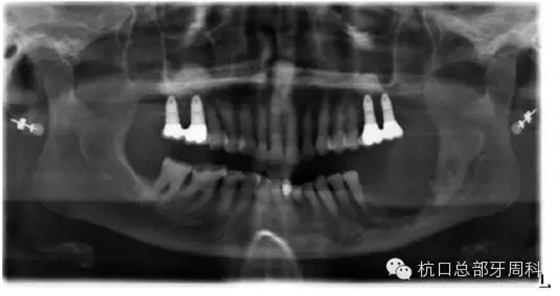

2012.4

2013.1

2013.3

下頜所有牙齒自動脫落,炎癥累及整個下頜骨,包括左側(cè)髁狀突,病理性骨折左側(cè)聽力喪失